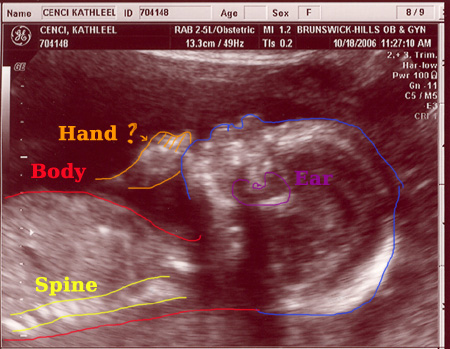

| On October 18, 2006 we had the second sonogram. The baby is growing well. It was moving quite a bit while we were watching. It is amazing to actually see feet, arms, ribs, the spine, we even saw it sucking it's thumb. Check out the photos below. Each one is clickable which will bring you to labeled versions to help you identify what you're looking at. Enjoy! |

Another Interpetation: Doing the Austin Powers "One MILLION DOLLARS!" Line